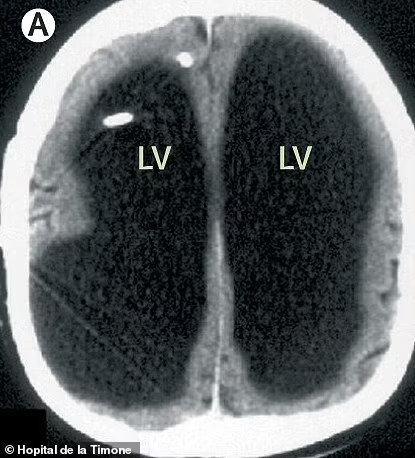

Šuntas vėliau buvo pašalintas, kai jam buvo 14 metų. Atlikus kompiuterinės tomografijos (KT) ir magnetinio rezonanso tomografijos (MRT) skenavimus, gydytojai buvo šokiruoti pamatę didžiulę skysčio ertmę ten, kur turėjo būti smegenys.

Nuotraukose, pasidalintose medicinos žurnale „The Lancet“, pagrindinė vyro smegenų sritis atrodo juoda, matosi, kur kaupėsi skystis.

Paciento smegenyse esantys nutekėjimo vamzdeliai susiaurėjo, dėl ko per dešimtmečius susikaupė skysčio perteklius.

Dėl to jo smegenys buvo suspaustos į ploną sluoksnį, spaudžiamą prie kaukolės krašto.